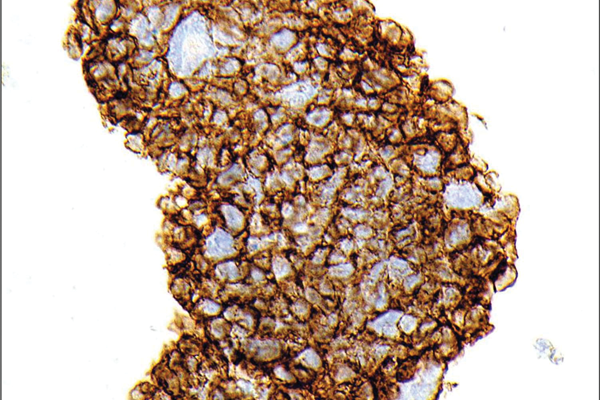

Pathology Quiz - Section Editor until Aug/Sep 2016